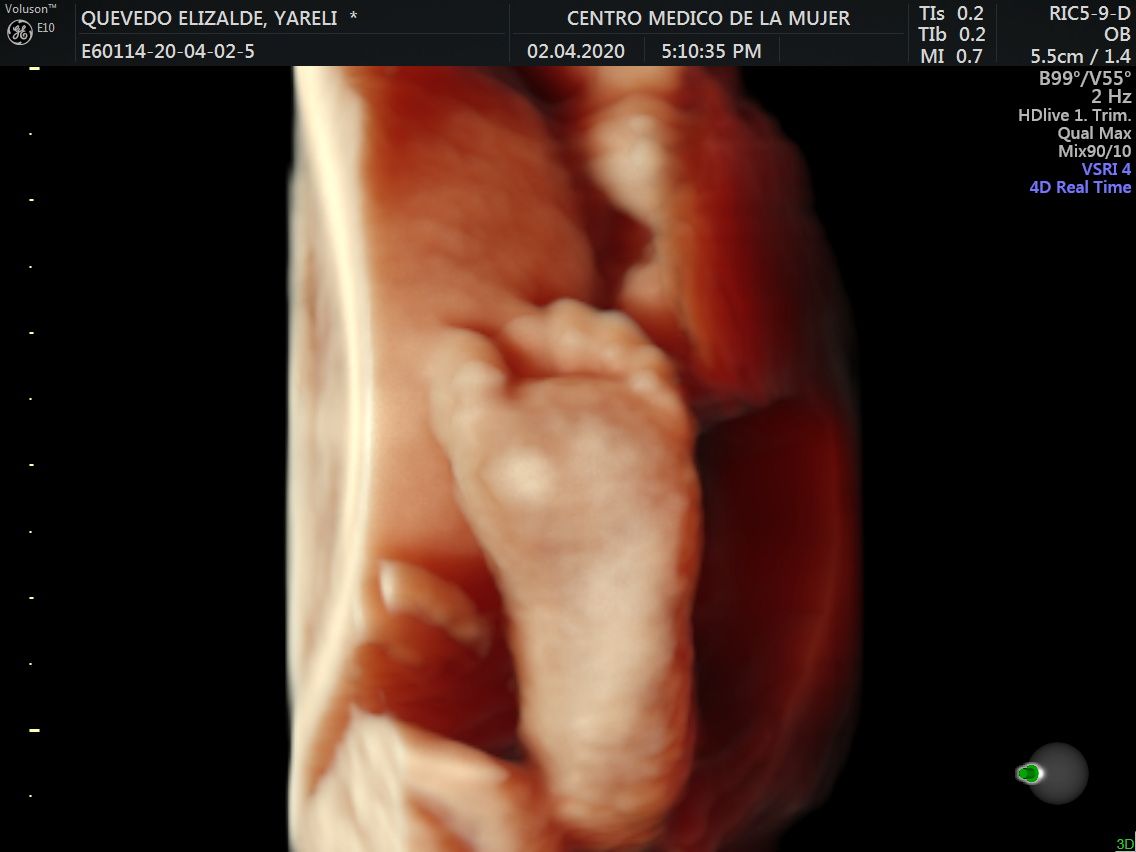

Fotos y videos

ECO Anatómico

Consiste en la evaluación especifica de cada organo y sistema del bebé con medidas detalladas de cada parte para evaluar su crecimiento proporcional.